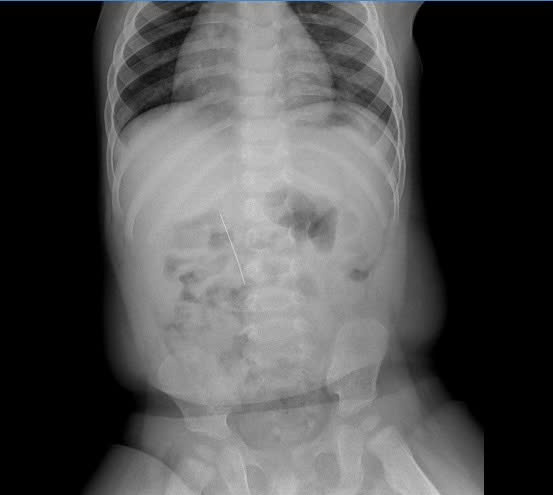

Tại Bệnh viện, sau khi thăm khám toàn trạng và làm xét nghiệm cần thiết, trẻ được chỉ định chụp X-quang bụng. Kết quả ghi nhận hình ảnh dị vật cản quang thẳng, dài, nằm ở vị trí tương ứng các đốt sống L1-L3, phù hợp với dị vật kim may nằm trong đường tiêu hóa. Trẻ lập tức được chẩn đoán T18 - Dị vật đường tiêu hóa và chuyển vào khoa Tiêu hóa để theo dõi, hội chẩn và xử trí cấp cứu.

Hình ảnh chụp X-quang cho thấy dị vật nằm trong ổ bụng rất rõ